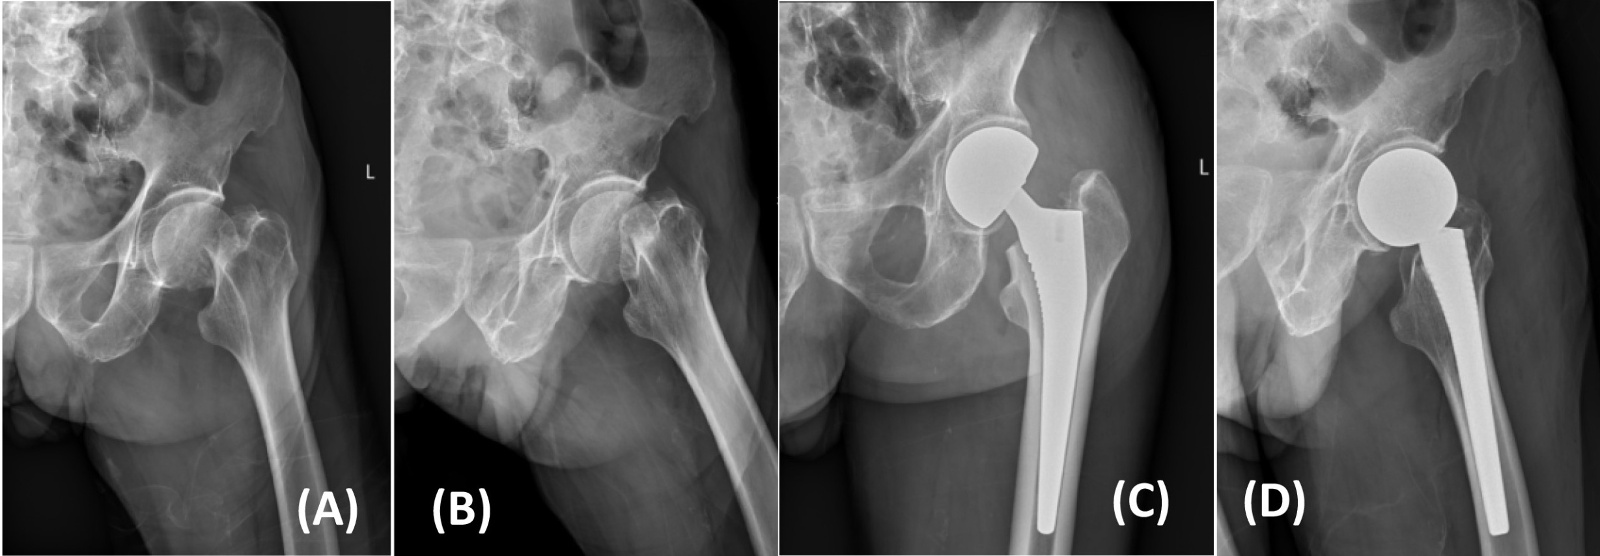

典型病例影像学表现见图1~5图1为70岁女性右侧股骨颈骨折(Garden Ⅲ型)患者,改良hardinge入路半髋关节置换术前X线示骨折断端部分错位,术后X线示假体位置良好;图2为85岁女性左侧股骨颈骨折(Garden Ⅲ型)患者,术后X线示假体位置良好;图3为83岁男性右侧股骨颈骨折(Garden Ⅲ型)患者,术后假体位置满意;图4为91岁男性左侧股骨颈骨折(Garden Ⅳ型)患者,术后假体匹配良好;图5为75岁女性左侧股骨颈骨折(Garden Ⅲ型)患者,术后假体位置正常,股骨近端微裂予钢丝捆扎固定。

Figure 2. X-rays before and after modified hardinge approach hemiarthroplasty in an 85-year-old female patient with left femoral neck fracture (Garden type III) (A), (B). Before operation; (C), (D). After operation

2. 85岁女性左侧股骨颈骨折(Garden III型)患者改良hardinge入路半髋关节置换手术前后X线片(A)、(B) 术前;(C)、(D) 术后